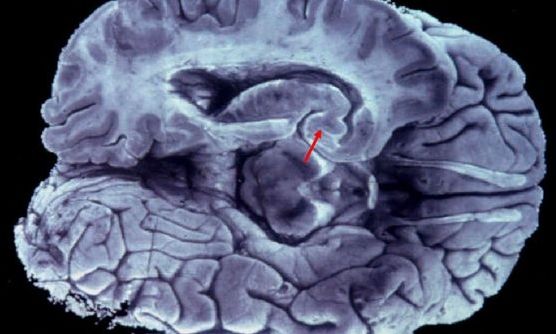

Μελετούν τον εγκέφαλο και ανακαλύπτουν τυχαία μυστηριώδεις δομές: «Αντιπροσωπεύουν ένα νέο πρότυπο»

Η ανακάλυψη ενός πιθανού νέου δικτύου αποστράγγισης στον εγκέφαλο από ερευνητές του Χάρβαρντ, ανοίγει τον δρόμο για νέες θεωρίες σχετικά… Περισσότερα...